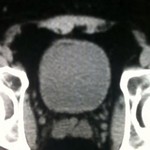

[バーチャル抄読会・AKBraves編](37) Fat Within the Wall of the Urinary Bladder: Computed Tomographic Appearance 2010-06-12

[バーチャル抄読会・AKBraves編](37) Fat Within the Wall of the Urinary Bladder: Computed Tomographic Appearance